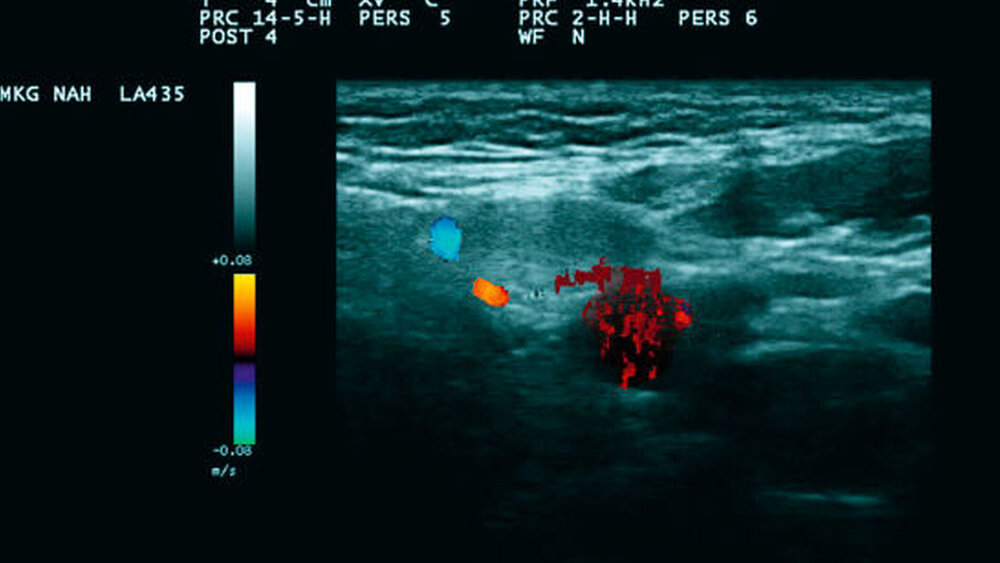

Somit stand differenzialdiagnostisch ein malignes Melanom im Raum. Vor diesem Hintergrund wurde bei sonomorphologisch einzelnen, ipsilateralen, aber zum Teil deutlich vergrößerten Lymphknoten (Abbildungen 2a und 2b) eine Sentinellymphknotenbiopsie durchgeführt, um für den potenziellen Fall des Vorliegens eines malignen Melanoms die Sicherheit für die Patientin zu erhöhen. Der Befund am Ohr selbst wurde zur Wahrung der Ästhetik als kleiner Keil entsprechend des atypischen spitzoiden Naevus entfernt (Abbildung 3).